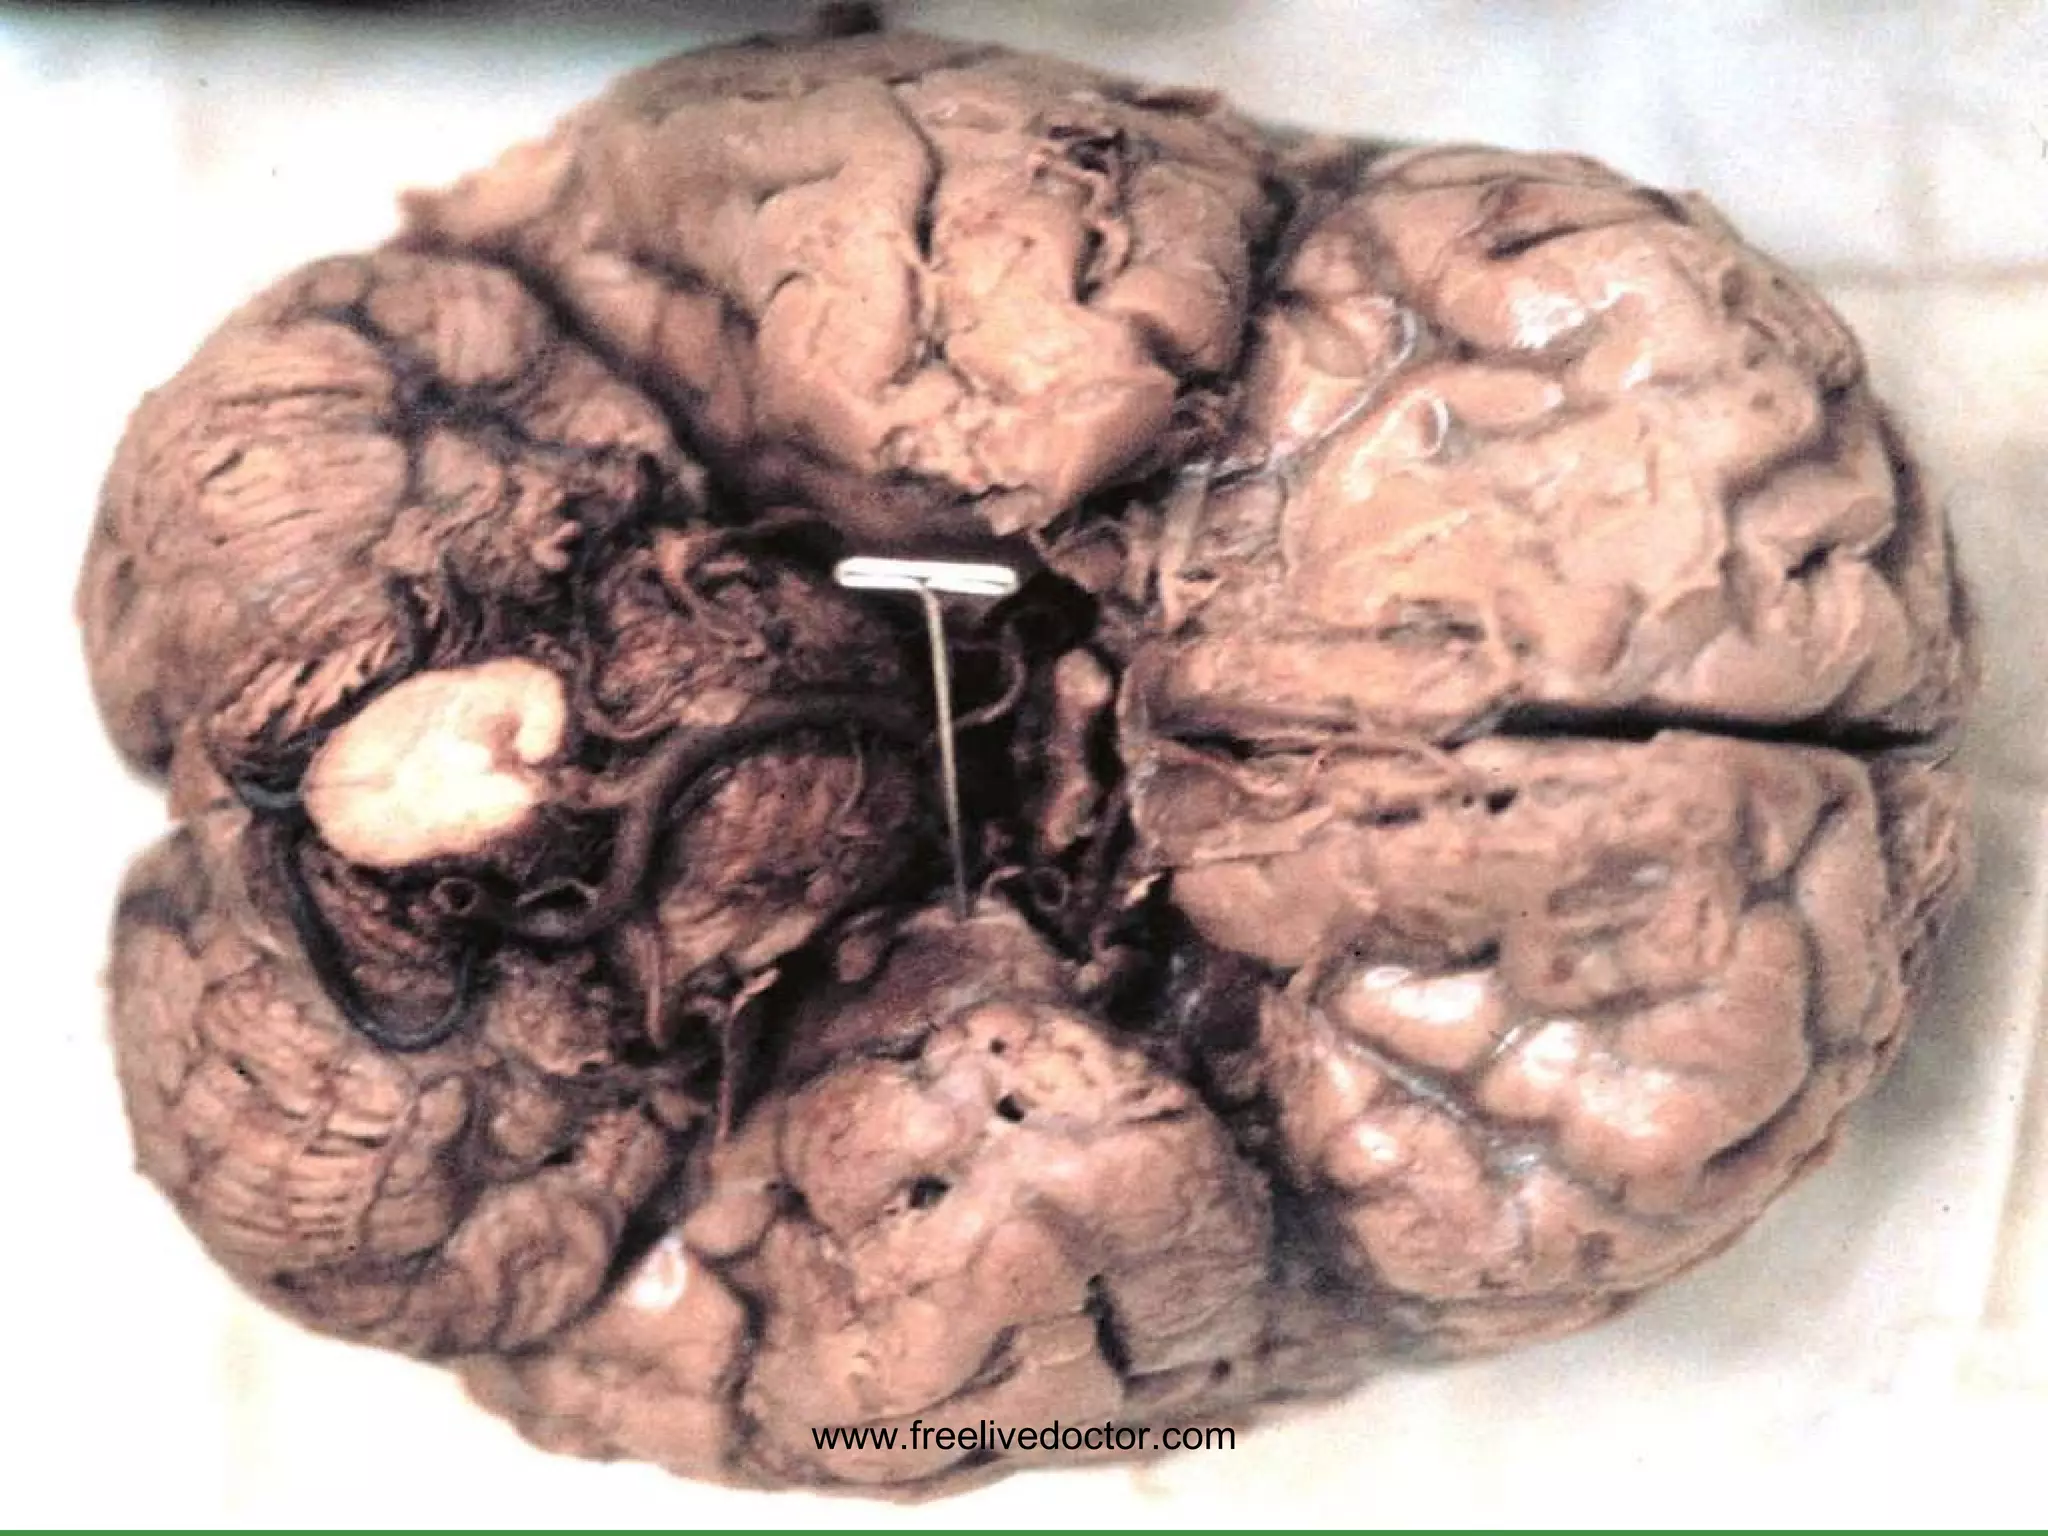

METASTATIC CNS TUMORS LUNG BREAST MELANOMA KIDNEY GI www.freelivedoctor.com

• #166 A solitary brain mass is statistically just as likely to be metastatic than primary

• #165 Toxoplasmosis and lymphomas and encephalitis are very common in AIDS. Might you cal the MRI lesion a “toxoplasmoma”? Ans: Sure